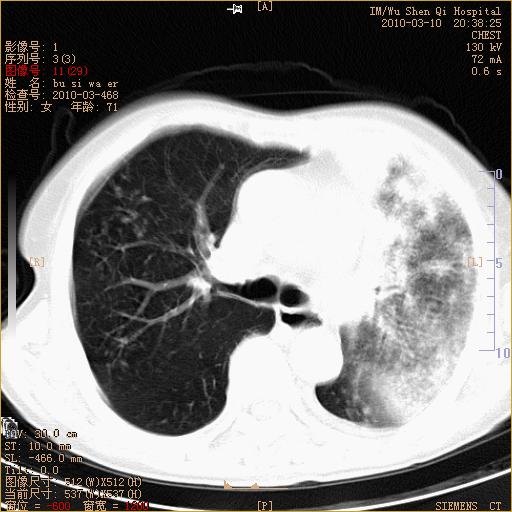

以下是引用随光逐影在2010-3-11 0:41:00的发言:[br]1)考虑左肺及右肺上叶继发性肺结核并左肺炎症感染。2)左侧支气管内膜结核可能;建议必要时行纤支镜检查。3)肺气肿。4)心包膜增厚(或少量心包积液)。5)左侧胸腔积液。